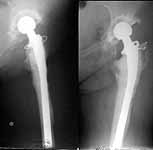

A female (birthdate 1948) was operated in 1995 because of the hip arthritis - THA (Phoenix). 1997 - revision THA with a cement Beznoska (the images attached). Recent weeks she marked pain in the femur and instability - xrays revealed stem migration and shaft fracture.

If a revision implant with super-long stem is not available, what plan is optimal? At the moment they plan to remove implant, cement, perform bone grafting of the proximal femoral end and nailing, and after healing of the shaft - nail removal and conventional revision THA.

Looking at the images your patient has an eggshell like bone filled with cement and prosthesis in the upper half. A longer stem would eventually land in a distal fracture, I feel. After you do removal of components, nailing and bone grafting why don't you keep her on traction and treat like an excision arthroplasty. This could be lesser of the evils. (Already two hip surgeries with one revision and one shaft fracture in seven years at the age of 54 years). An interesting problem for Surgeons from less developed countries since we can't go on revising hips forever due to non availability of components and economics.

The hip may be infected, in which case all the previous answers may apply. If during operation there is no infection, I wonder if you could remove the stem, insert a new shorter one with cement, apply a wave plate from the proximal cement to the distal femur and graft the part in the middle?